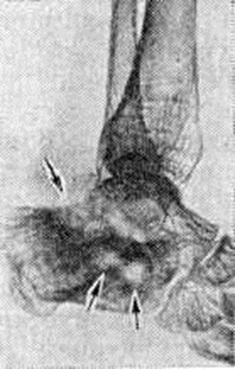

В других случаях наблюдается инкапсуляция гнойников в кости. К 3—4-й недель от начала заболевания при рентгенологическое исследовании на фоне рарефикации определяются очаги некроза кости, поскольку омертвевшая кость не подвергается резорбции и сохраняет прежнюю плотность. При патологоанатомическом исследовании участки некроза выявляются ещё раньше. В дальнейшем те из них, которые находятся в самом очаге нагноения, подвергаются секвестрации (рисунок 1). Секвестрация (смотри полный свод знаний Секвестр, секвестрация) заключается в отторжении омертвевших участков кости, находящихся в полости гнойника, от окружающей костной ткани. При этом в случае образования секвестра в компактной пластинке на её поверхности в зоне прилегания грануляций возникает и постепенно углубляется секвестральная борозда, а в толще — расширение гаверсовых каналов и слияние их между собой. После того как все костное вещество в указанной зоне растворится, секвестр оказывается свободно лежащим в полости гнойника (цветной рисунок 2 и 3). Секвестры губчатого вещества кости отделяются от остальной её части за счёт растворения прилежащих костных балок, находящихся в зоне грануляций (рисунок 2).

Воспаление начинается в мягких тканях краёв раны в виде диффузной воспалительной инфильтрации, вслед за которой на границе с зоной омертвения формируется демаркационная линия. Одновременно образуется экссудат, поступающий в полость раны и пропитывающий некротизированные ткани, подвергающиеся при этом расплавлению, а часто и гнилостному распаду. К 4— 5-му дню в зоне демаркационной линии образуются грануляции, обильно продуцирующие гной. К этому сроку проявляется и гнойное воспаление в отломках кости, которое протекает на границе с некротизированными тканями, сохраняя характер демаркационного. С началом нагноения омертвению могут подвергнуться связанные с периостом костные осколки и мягкие ткани, испытавшие коммоцию — зона резерва некроза по И. В. Давыдовскому. Очаг нагноения постепенно изолируется валом из грануляций, а в последующем и соединительнотканной капсулой. В нем располагаются свободные костные осколки, не удалённые при хирургической обработке раны, осколки, сохранившие связь с периостом, концы отломков, лишённые периоста, инородные тела, обрывки мягких тканей, распадающиеся кровяные свёртки (рисунок 3). Нагноение нередко распространяется в глубь мягких тканей и в толщу кости вдоль трещин и каналов, проделанных сместившимися в момент ранения костными осколками, что придаёт очагу сложные очертания (цветной рисунок 1).

В ходе нагноения происходит расплавление омертвевших тканей под действием ферментов гноя и выделение их из раны, а также секвестрация омертвевших участков кости, находящихся в очаге нагноения. Темпы секвестрации снижаются при обширном параоссальном нагноении, задержке гноя в ране, тяжёлой интоксикации.